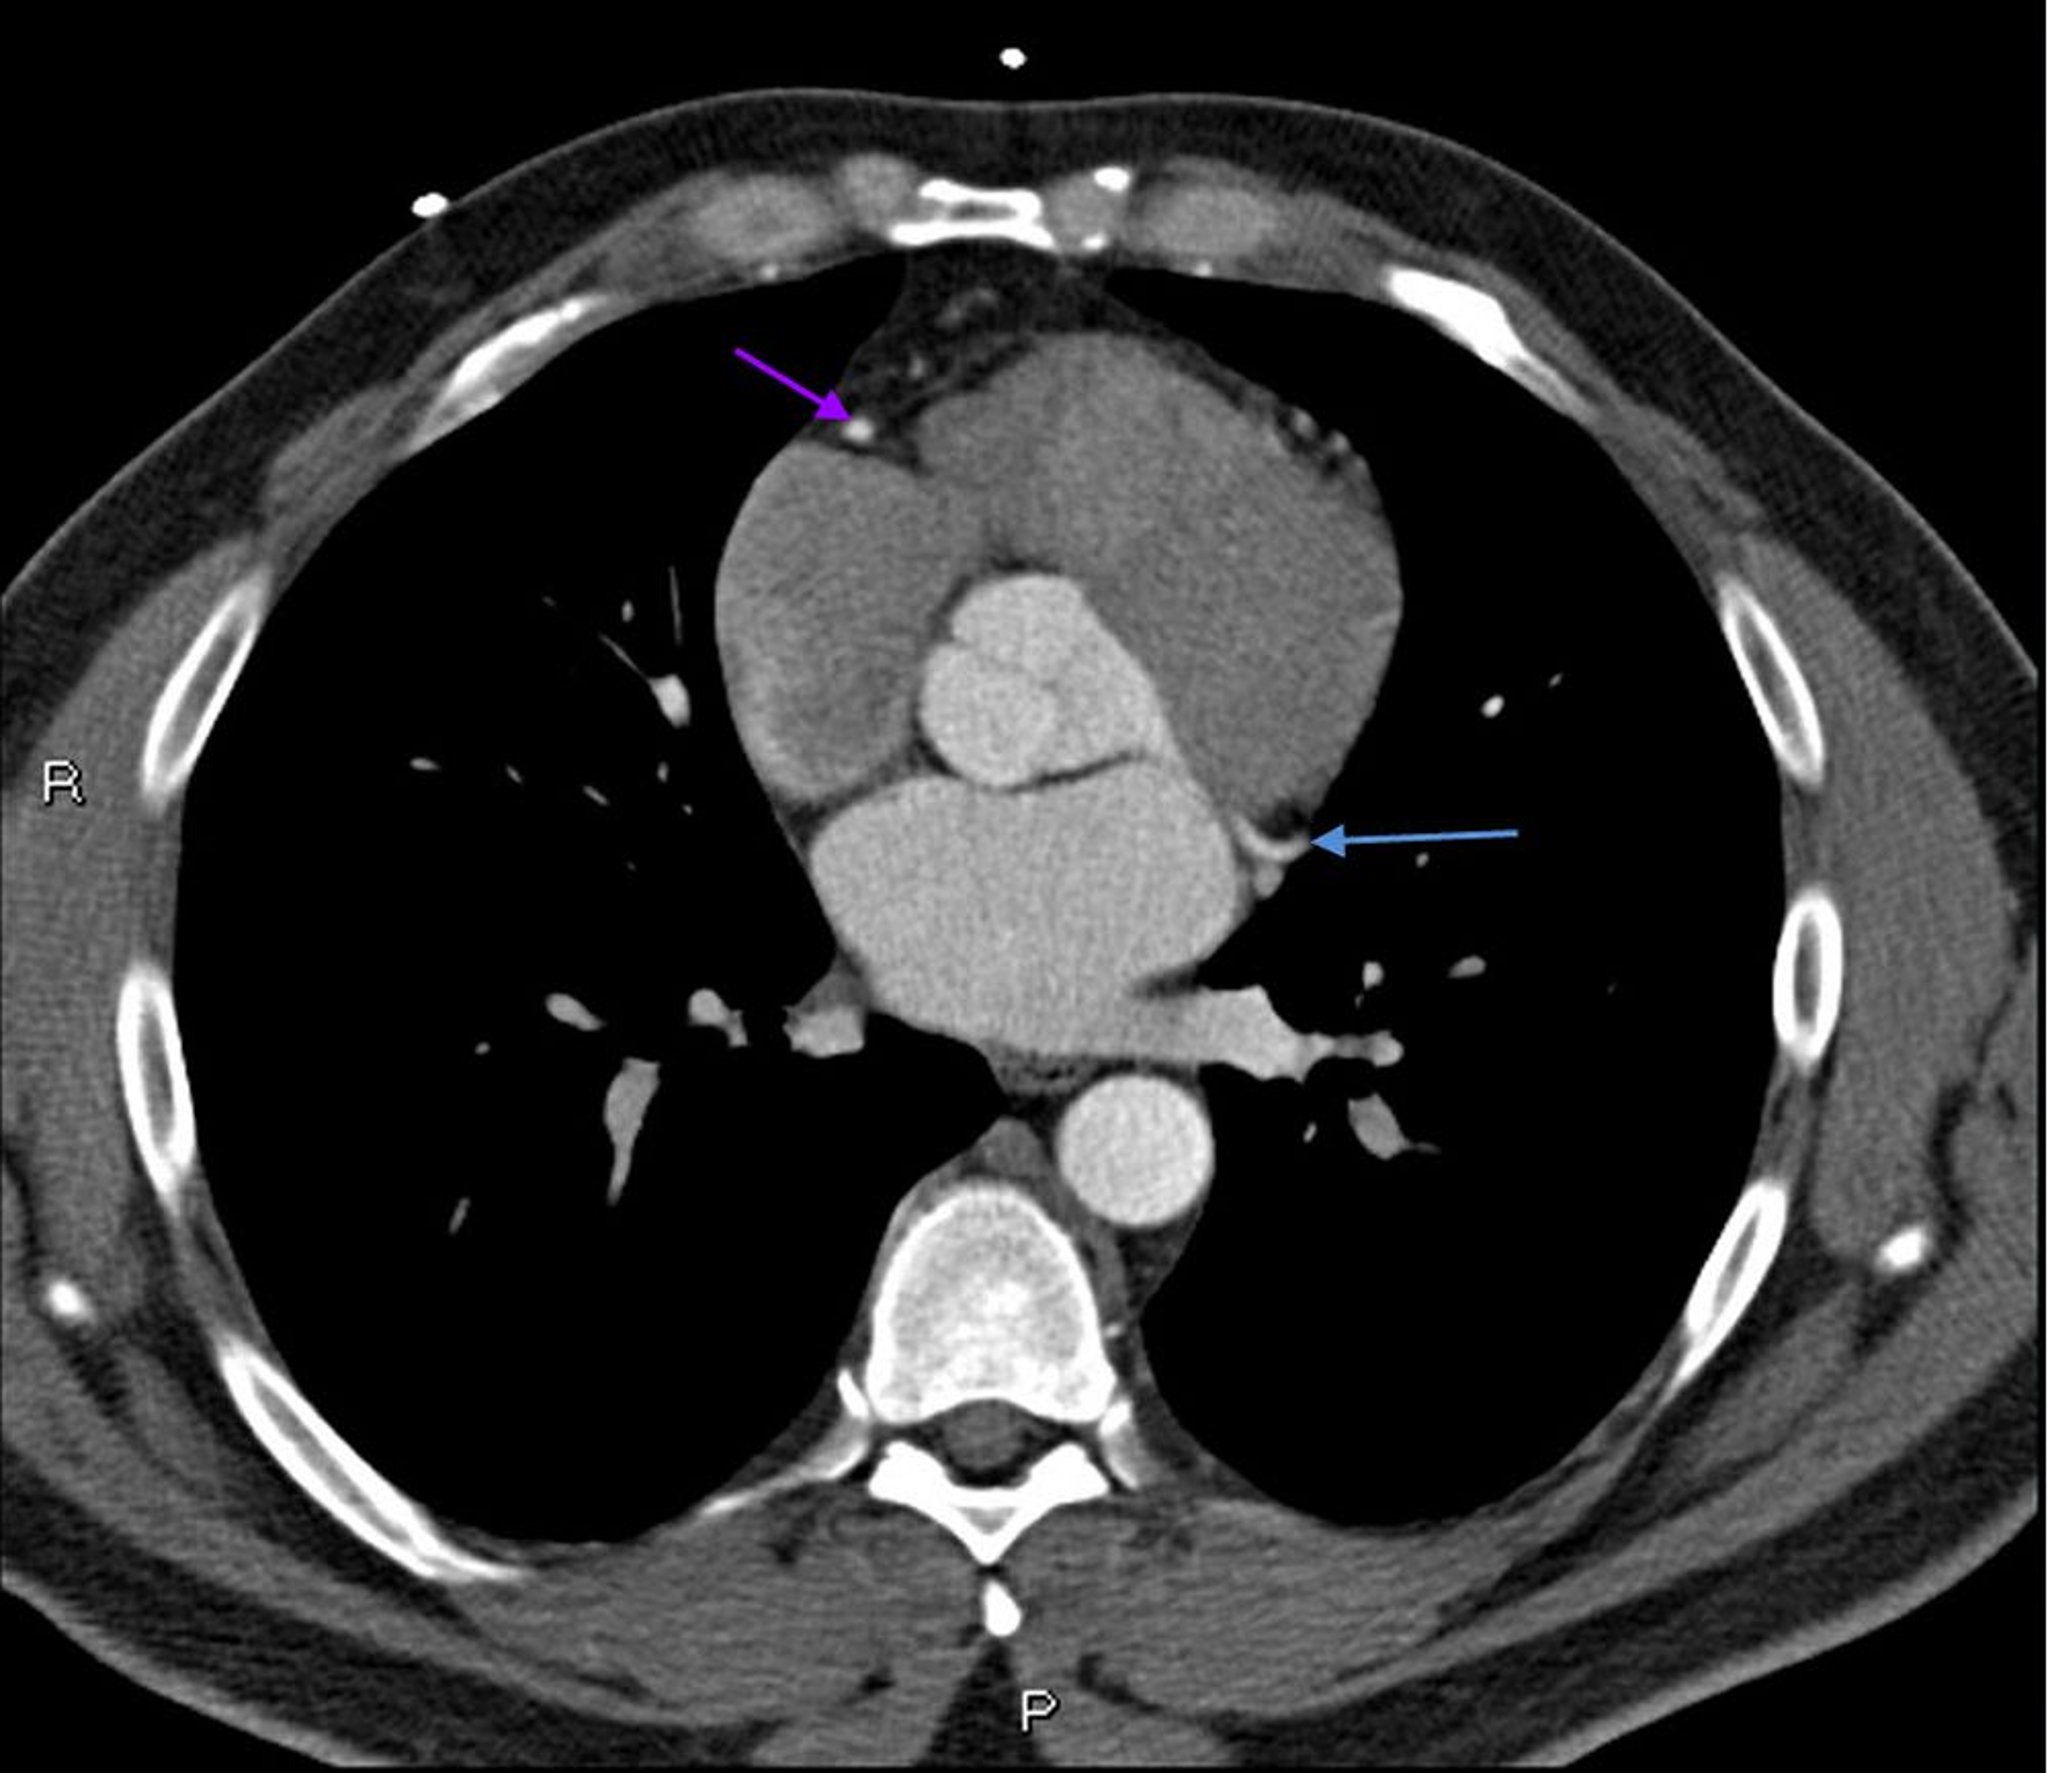

Tomografía computarizada con contraste que muestra arterias coronarias normales–diapositiva 6

Esta TC con contraste muestra arterias coronarias normales. La arteria principal izquierda está indicada por la flecha roja. Las arterias descendente anterior izquierda y circunfleja izquierda están indicadas por las flechas verde y azul respectivamente, y la arteria coronaria derecha está indicada por la flecha púrpura.